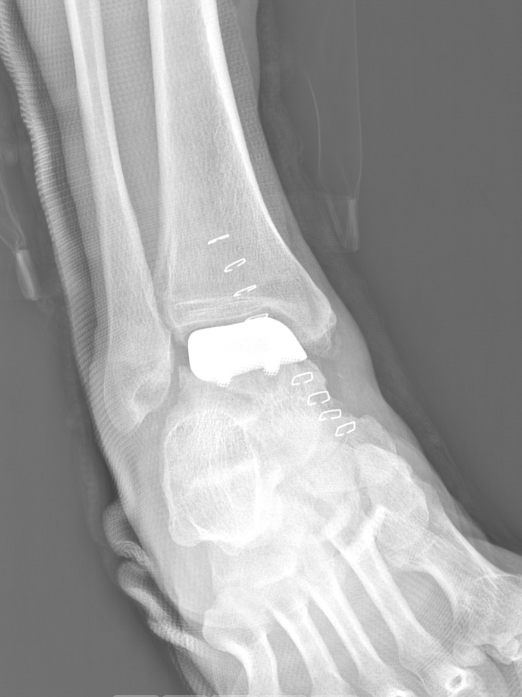

术前踝关节正位X线

术后正位X线